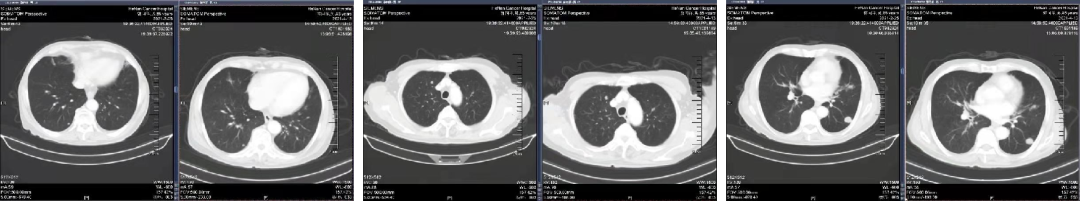

于2021.04.14 始行“曲氟尿苷替匹嘧啶片(TAS-102)+贝伐珠单抗”2周方案治疗至今。

04 疗效评估

患者疾病控制良好,耐受情况好。